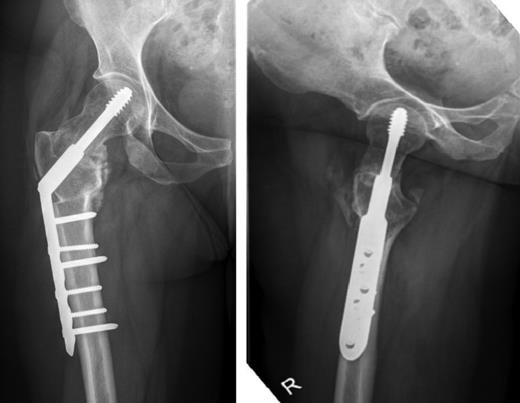

Anterior-posterior and lateral radiographs taken 6 months postoperatively demonstrating union of the fracture and osteotomy site.